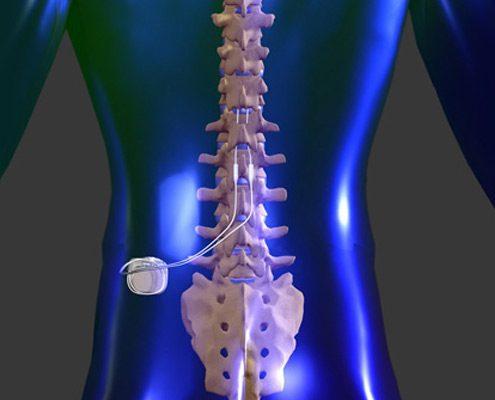

Spinal Cord Stimulation

Spinal Cord Stimulation (SCS)

SCS involves implanting a device that sends electrical impulses to the spinal cord, blocking pain signals. It is typically used for conditions like failed back surgery syndrome and neuropathic pain. A trial period with an external stimulator precedes permanent implantation.